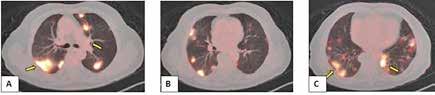

Figura 1. (Izq.) radiografía de tórax en proyección anteroposterior (AP) al ingreso en UCI-N para comprobación de sonda nasogástrica sin hallazgos significativos. (Der.) Radiografía de tórax AP a las 16 horas de vida donde se objetivan tenues focos de aumento de densidad de distribución difusa, alguno de ellos, como el localizado en campo superior izquierdo, con broncograma aéreo.

Figura 2. (Izq.) radiografía de tórax en proyección AP a las 36 horas de vida donde se objetiva neumotórax de nueva aparición (flechas azules) y una zona de hiperclaridad alrededor de la silueta cardíaca que sugiere importante neumomediastino (estrellas amarillas). (Der.) TC de tórax sin contraste intravenoso en ventana de pulmón que confirma la presencia de neumomediastino (estrella amarilla). Se objetivan focos de consolidación periféricos y bandas lineales de densidad aire paralelas y adyacentes a las vainas broncovasculares (flechas amarillas).

Figura 3. TC de tórax sin contraste intravenoso en ventana de pulmón a los 9 días de vida sin alteraciones en el parénquima y neumomediastino prácticamente resuelto.